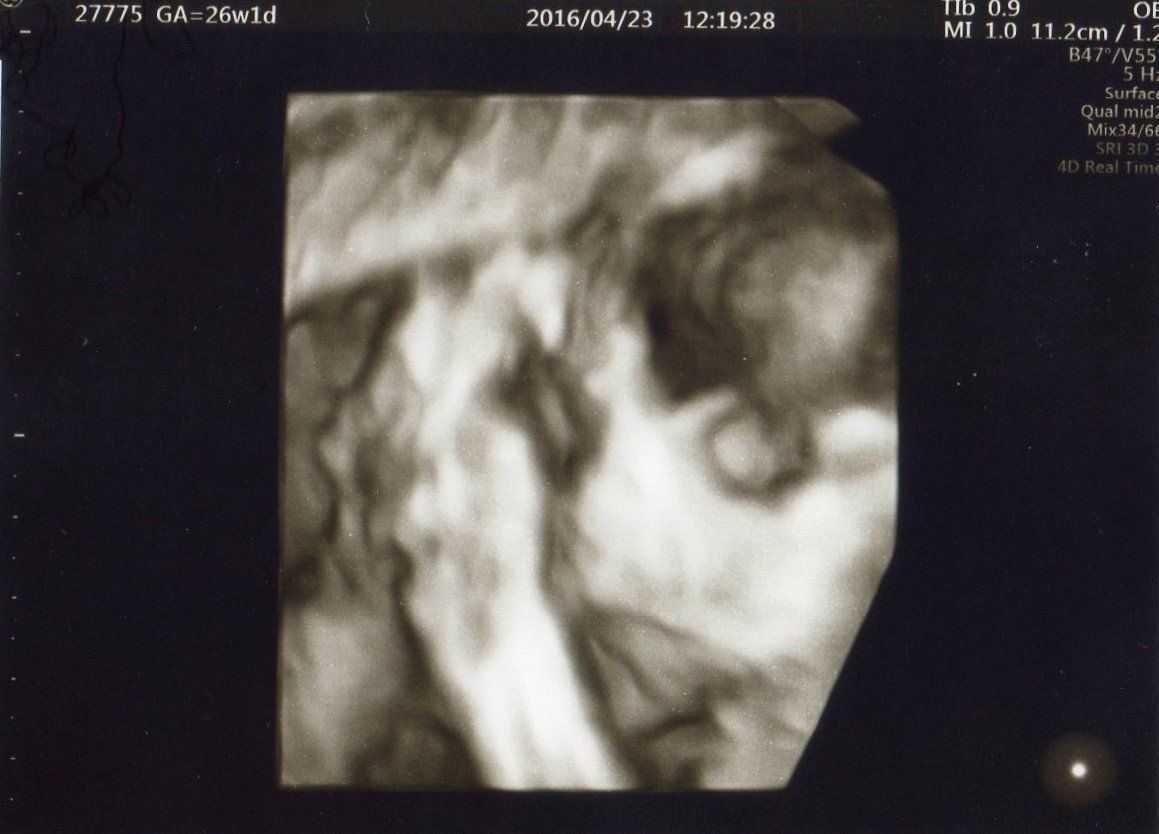

妊娠26週目 女の子らしい顔つきになってきました!

妊娠26週目。写真左側が両手、右側が顔。両手を合わせてすやすやと眠る姿が見えます。優しい顔つきを見て、夫と「きっと女の子だろうね」と予想しました。この時期から、マタニティスイムやヨガの教室へ通い、呼吸法でリラックスして力を抜く練習をして出産に備えました。